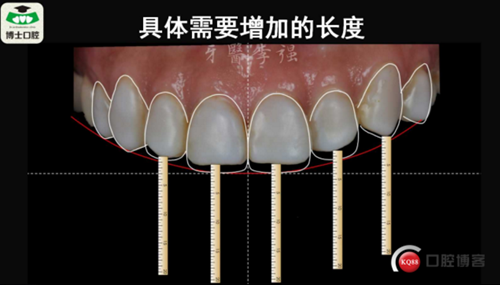

樹(shù)脂貼面與瓷貼面的孰是孰非~牙醫(yī)李強(qiáng)(濟(jì)南博士口腔)

樹(shù)脂貼面與瓷貼面的孰是孰非~牙醫(yī)李強(qiáng)(濟(jì)南博士口腔)

樹(shù)脂貼面與瓷貼面的孰是孰非~牙醫(yī)李強(qiáng)(濟(jì)南博士口腔)